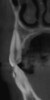

Fig 13 and Fig 14.

Pre- and post-SFOT dentoalveolar

bone presentation. Note the

facial bone augmentation and improved

incisor angle relationship.

Figure 13

Fig 13 and Fig 14. Pre- and post-SFOT dentoalveolar bone presentation. Note the

Figure 14